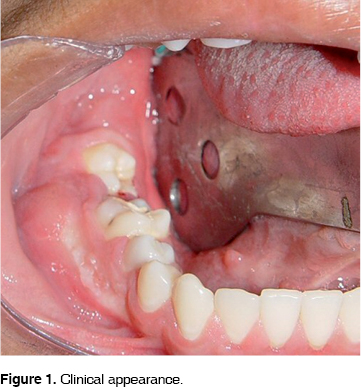

A 14 year old boy was admitted to the dental clinic at the Hospital Juárez de México in July 2004, with a right mandibular tumor like lesion, of apparently 7 months of evolution. The patient reported tenderness and there was no other relevant history for this lesion. The swelling was located from the right second premolar to the third molar zone with vestibular expansion with displacement and mobility of the first and second molar ipsilateral (Figure 1). The panoramic radiograph showed a unilocular radiolucid lesion that extended from the first and second right molars with a very close relation to the third molar, well defined borders and measuring approximately 30 x 20 mm, producing displacement of the teeth involved (Figure 2). The simple CT scan showed a lesion that produced vestibular and lingual cortical slimming and expansion with preservation of the mandibular border (Figure 3).